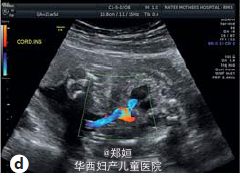

22岁初产妇,孕21周,因胎儿膀胱未见、羊水过少、胎儿腹部囊性结构就诊

B超提示羊水过少和未见胎儿膀胱,肾窝内未见肾脏,但是在腹腔和盆腔可见三个囊性结构,外生殖器性别不明 胎儿MRI提示有泌尿生殖器畸形

临床诊断为胎儿泌尿生殖器畸形 患者要求生产,在孕35周,顺产生下一3140g男婴